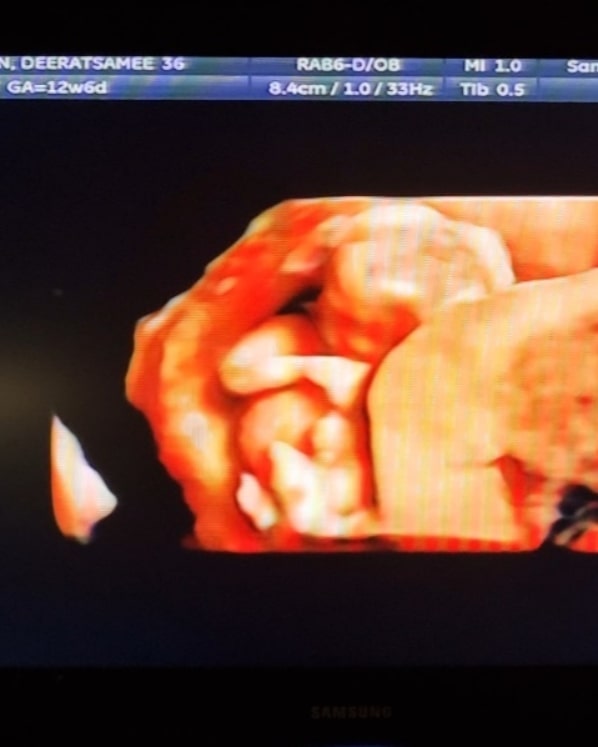

Merry Xmas Eve 2021🎄 with our best gift this year 👶🏻 Bride & Groom / Mom & Dad, to be 👰🏻♀️💗🤵🏻

พ้นช่วงลุ้นระทึกมาแล้ว เข้าสู่ไตรมาส 2 แล้วประกาศได้ 😁

ก่อนหน้านี้มีสถานการณ์ให้ลุ้นมาก ว่าเจ้าจิ๋วจะอยู่กับเรารึเปล่า.. ต้องนอนนิ่งๆอยู่บ้าน แคนเซิลงานทุกอย่าง ไปอาทิตย์นึงเลย 😅 (เดี๋ยวมาลงคลิปเล่าให้ฟังค่ะ)

แต่ทุกอย่างก็ผ่านพ้นไปด้วยดี น้องปลอดภัย แข็งแรงค่ะ เลยมาประกาศข่าวดีซะเลย เป็นของขวัญวันอีฟปีนี้ของพวกเราค่ะ 🥰 เป็นแฟนกันมา 4 ปี พรุ่งนี้จะเปลี่ยนสถานะเป็นสามี ภรรยา และ คุณพ่อ คุณแม่ละน้าา 💗💗